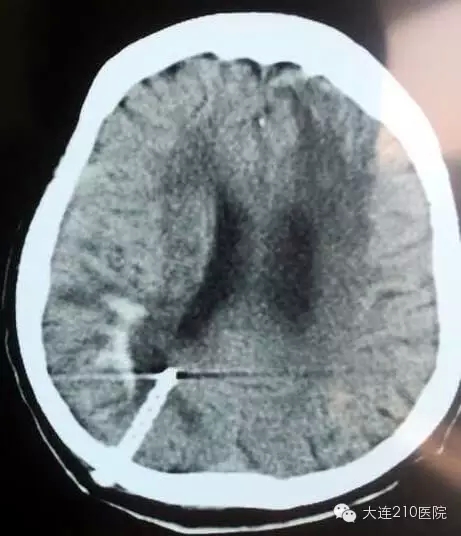

考虑到患者卧床三日未进水食,生命体征紊乱并伴有严重肺部炎症,难以耐受全身麻醉,神经外科陈岩主任了解病情后,建议采用本科特色技术——颅内血肿立体定向钻孔引流术,局部麻醉条件下,仅用一根软管排出颅内血肿。

立体定向引流术后 仅用一根软管排出颅内血肿